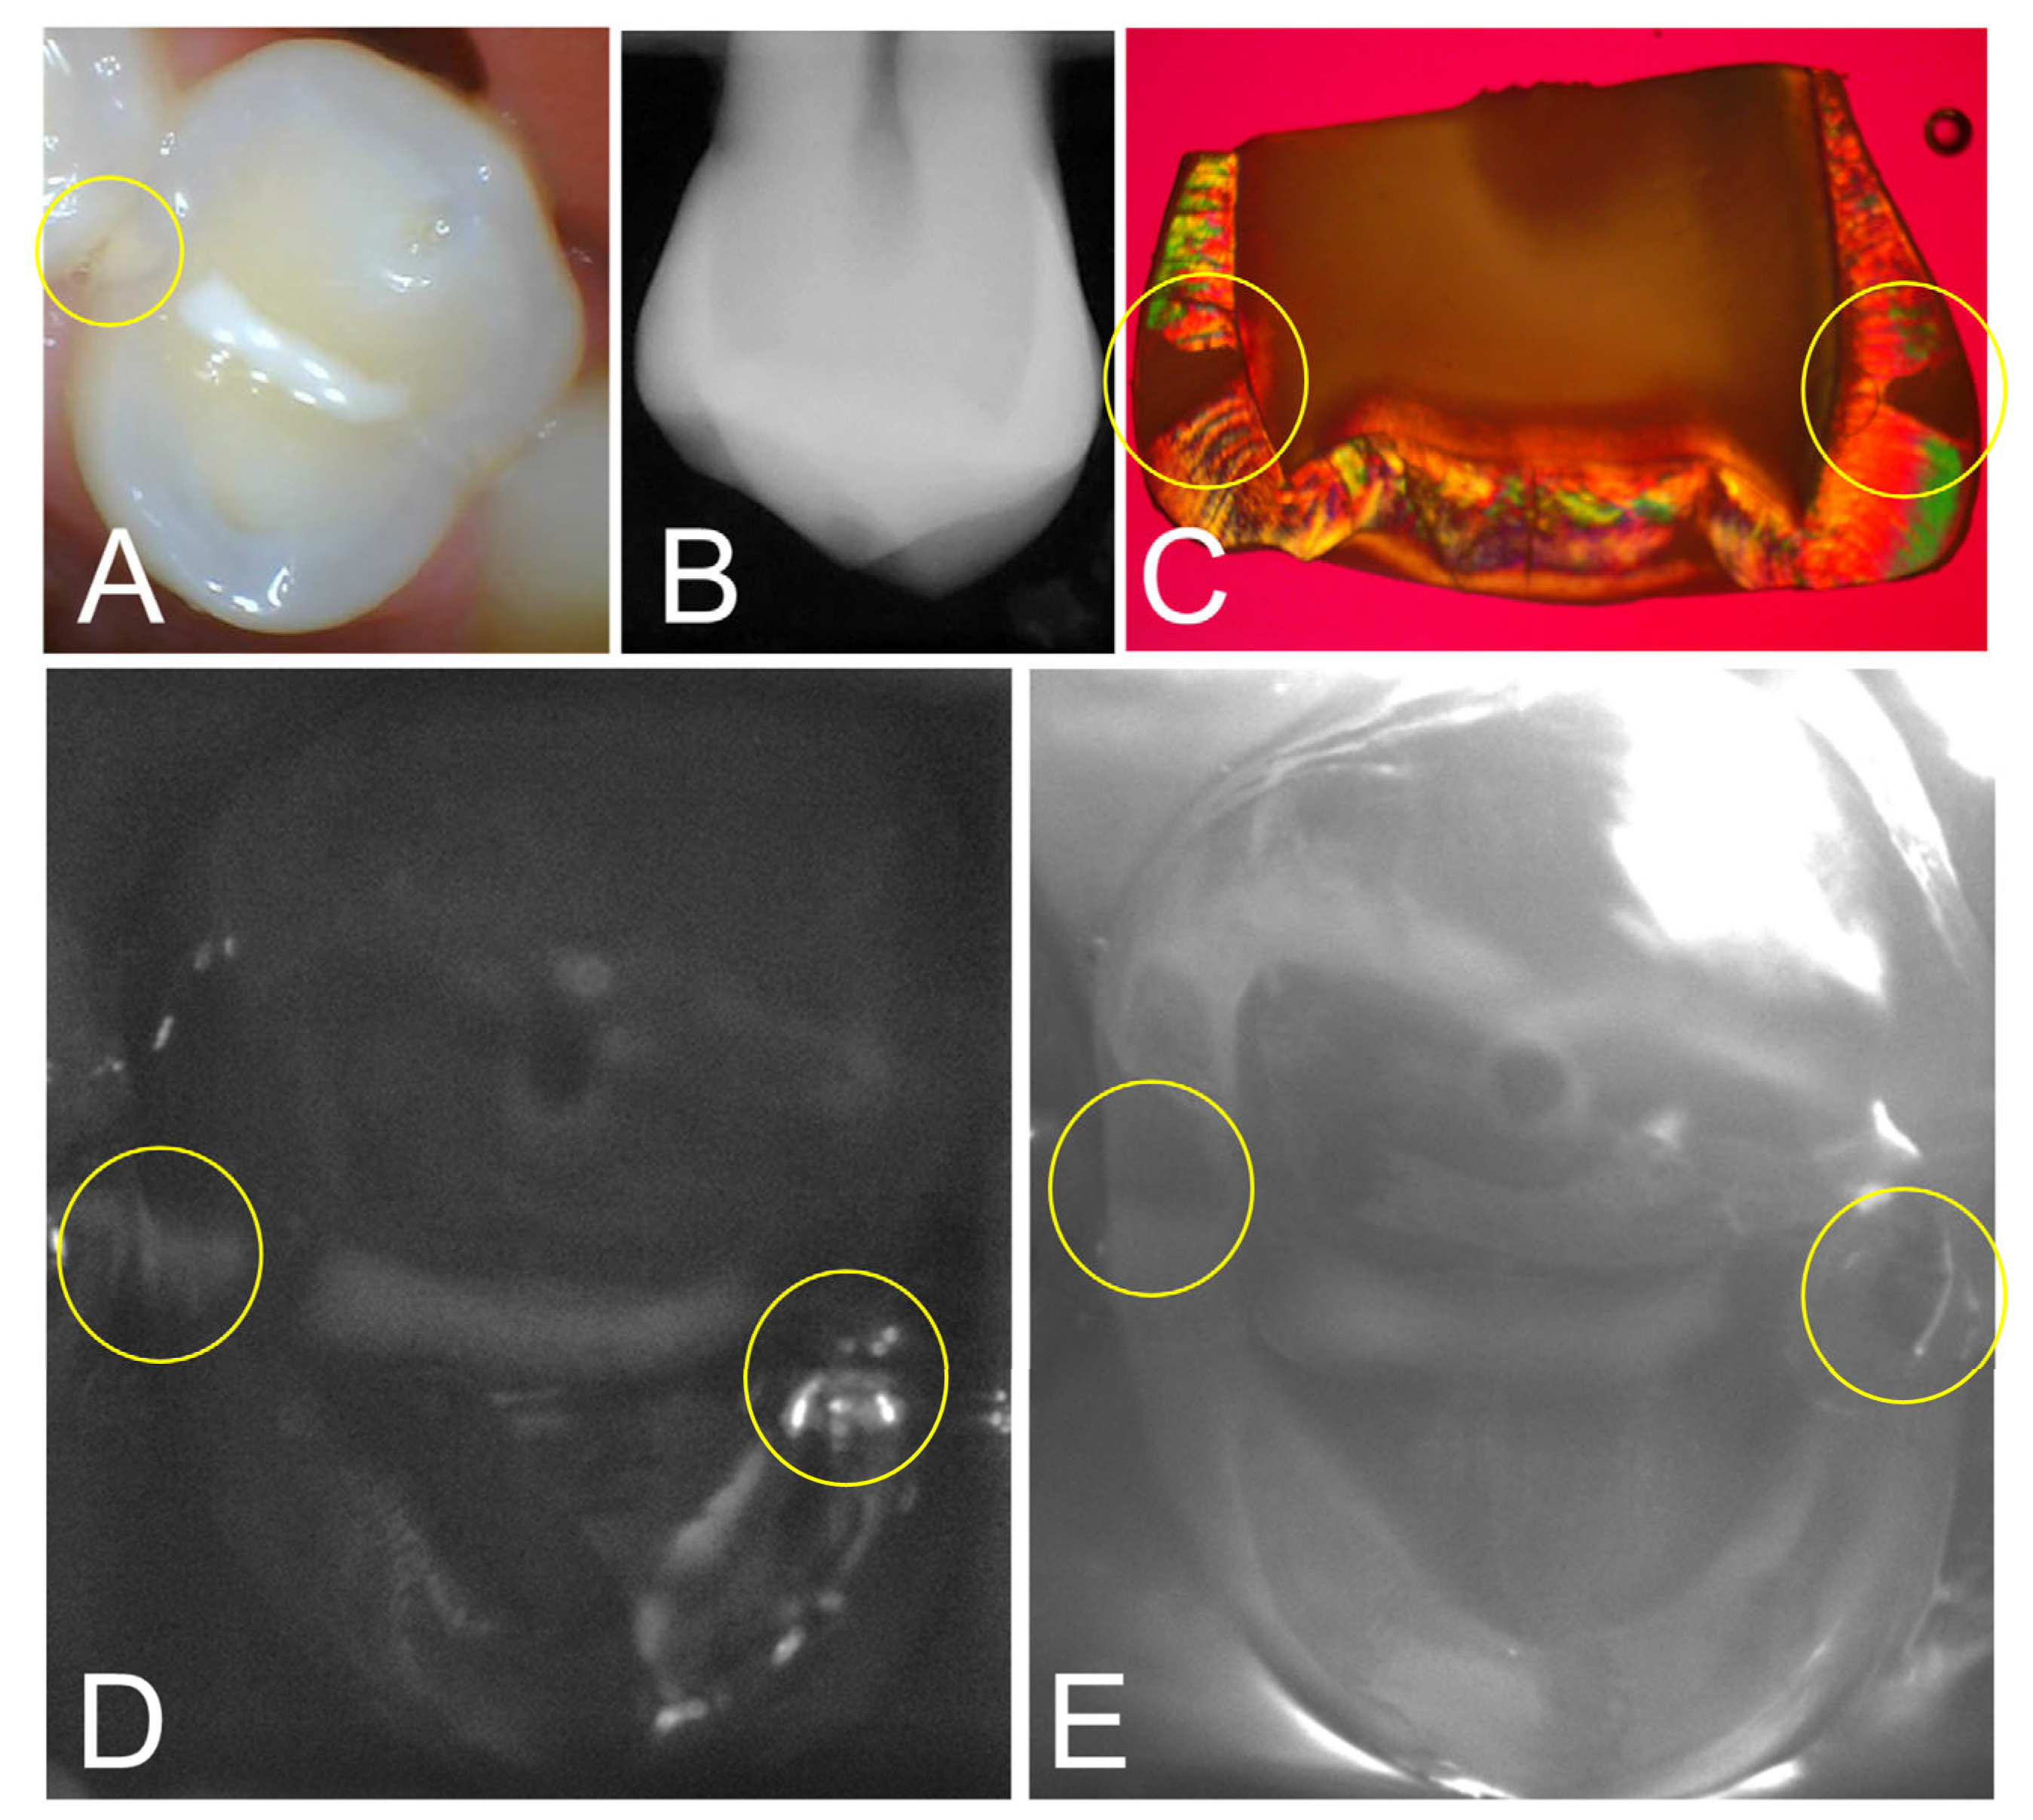

Images from one tooth from the study with two interproximal lesions are shown in Figure 2. The color image in Figure 2A shows a bicuspid with a sealant on the occlusal surface along with a visible lesion on the distal surface. Neither lesion is obvious in the radiograph in Figure 2B. Only one of the three clinical examiners detected the lesion on the distal surface in the radiograph and by visual examination and none identified the lesion on the mesial surface by radiograph or visual examination. After tooth extraction and sectioning, PLM in Figure 2C shows that lesions are present on the distal and mesial surfaces. The SWIR reflectance and occlusal transillumination images acquired with the dual probe are shown in Figure 2D,E and both lesions are visible in the yellow circles.

Figure 2. (A) Color image of a bicuspid with a sealant on the central fissure; a lesion is visible at the distal contact, while no lesion is visible at the mesial contact. (B) The radiograph shows no obvious lesions. (C) PLM image of a section cut from the tooth after extraction shows proximal lesions on both surfaces (yellow circles). (D) SWIR reflectance and (E) occlusal transillumination images show lesions on both surfaces.